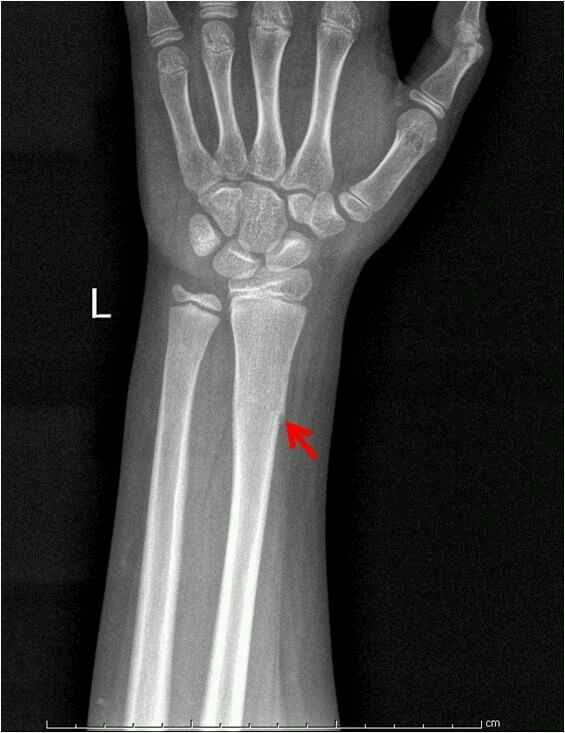

青枝骨折++b.右尺骨骨折